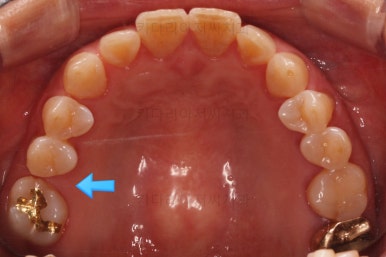

어금니를 뒤로 밀어주기 위해서 미니스크로와 브라켓, 철사를 이용해줍니다.

중간중간 장치 디자인이나 미니스크류의 위치를 바꿔주기도 합니다.

점점 자리가 확보되어가는게 보이시죠?